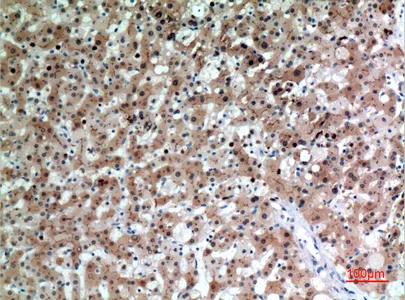

CD1D Rabbit Polyclonal Antibody

Cat: APRab08263

Size1:50μl Price1:$118

Size2:100μl Price2:$220

Size3:500μl Price3:$980

Size2:100μl Price2:$220

Size3:500μl Price3:$980